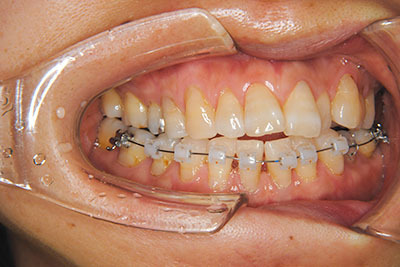

おとなの方でも矯正治療をあきらめないでください!

いくら歯が動き易くとも、本人がやる気でなければ効果は出ませんし、むし歯発生のリスクも高まります。おとなの方は顎の成長が終わっているため、治療の計画が立てやすいとも言えます。「もう大人だから…」とあきらめず、一度ご相談ください。